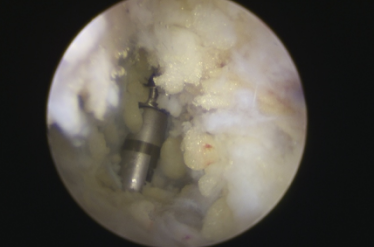

镜下打入锚钉固定距腓前韧带

术中,探查见关节腔大量增生病变滑膜组织,距骨软骨面多处软骨剥脱变性,明显的外侧副韧带损伤后继发关节炎表现。手术医生在踝关节镜下刨削刺激病变的距骨软骨,打入锚钉固定距腓前韧带,圆满完成手术。